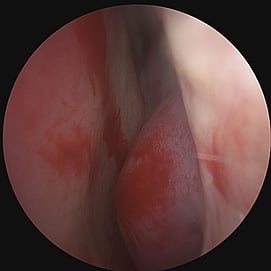

Turbinate Reduction

Turbinate reduction for obstructive sleep apnea is a surgical procedure aimed at improving nasal airflow and reducing upper airway resistance during sleep, thereby potentially alleviating symptoms of OSA. The turbinates are structures inside the nose that help humidify and filter air as it passes through. In the case of turbinate enlargement (hypertrophy), they can contribute to nasal congestion and obstruction, which may exacerbate or contribute to sleep-disordered breathing.